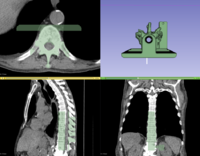

Slicer4 Radiation Therapy Tutorial

• The SlicerRT tutorial is an introduction to the Radiation Therapy functionalities of Slicer.

• Author: Csaba Pinter, Andras Lasso, An Wang, Gregory C. Sharp, David Jaffray, Gabor Fichtinger.

• Dataset: download from MIDAS server

• Based on Slicer 4.7